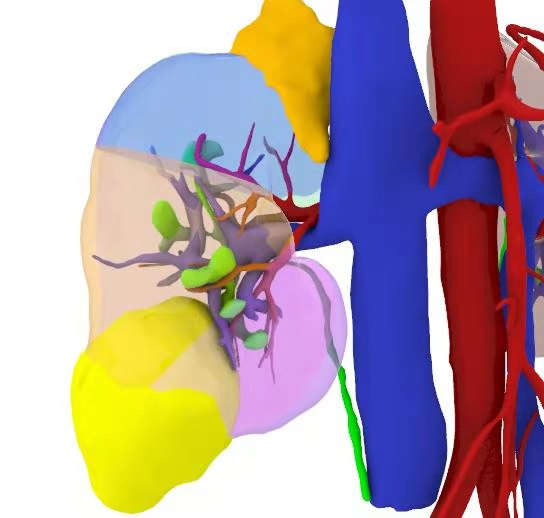

患者,女性,36岁。因10天前体检彩超发现右肾实质性占位病变,进一步行增强CT检查提示“1.右肾占位,轻度强化;性质待定,拟肿瘤性病变可能,肾癌(乳头状肾细胞癌)?建议结合临床相关性实验室检查。”。为进一步手术治疗入院。术前为患者行全息影像重建做好手术规划,考虑肿瘤局限,适合行肾癌部分切除术(单纯切除肿瘤而保存大部分健康的肾脏实质)。患者恢复良好,术后4天出院。术后病理提示右肾嫌色细胞癌。

术前全息影像所见